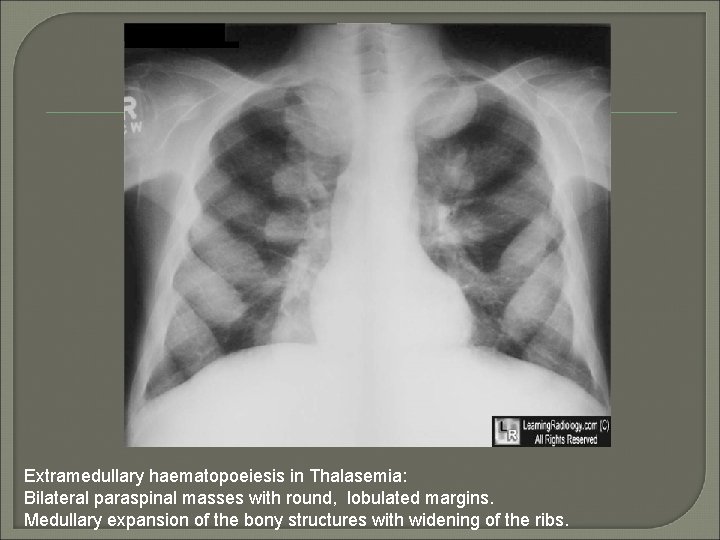

Extramedullary haematopoeiesis in Thalasemia: Bilateral paraspinal masses with round, lobulated margins. Medullary expansion of the bony structures with widening of the ribs.